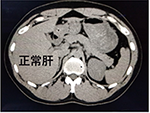

症例2:脂肪肝

脂肪肝は肝臓に中性脂肪が多く蓄積する状態で放っておくと肝炎から肝硬変、肝がんへ進行することもあります。

画像では正常な肝臓に比べて脂肪肝の方が黒く見えます。